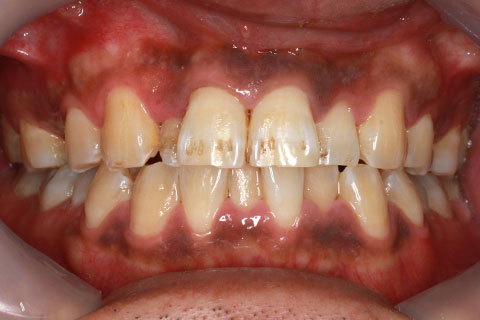

オールセラミックの症例2

- 年齢・性別

- 45歳男性

- 治療期間

- 2ヶ月

- 抜歯

- なし

- 治療費

- 70.4万円

- 備考

- 前歯8本の歯列不正によるセラミック治療

- 治療内容

- 歯質を削除し、セラミック冠をセメント合着

- 施術の副作用(リスク)

- 知覚過敏、歯髄炎、荷重負担